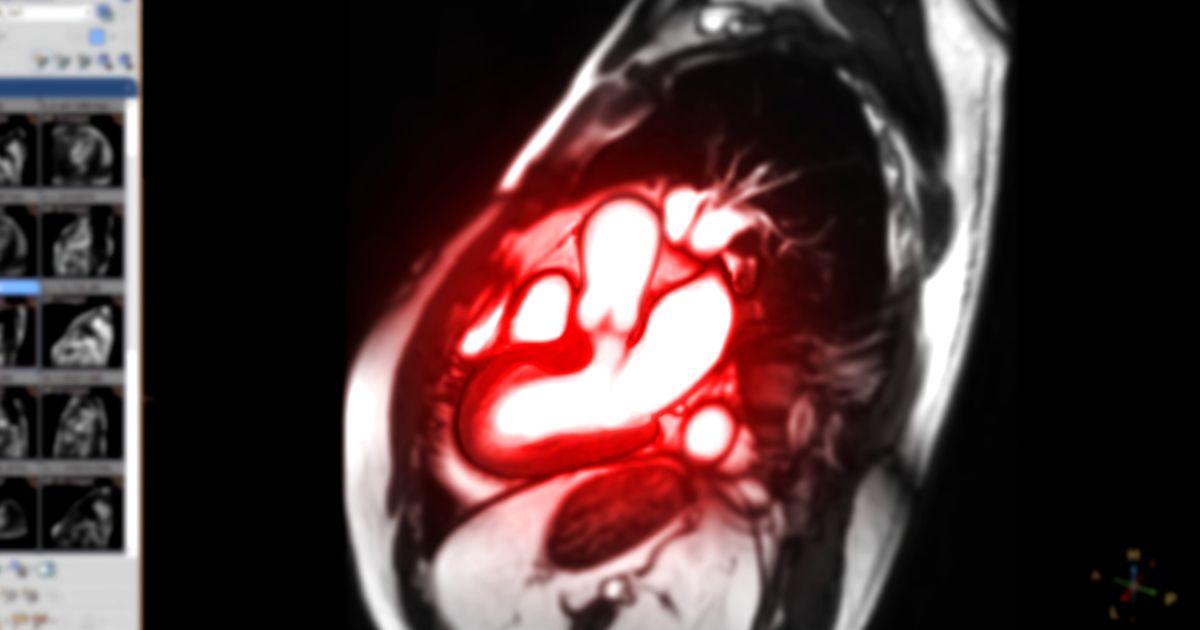

Η μαγνητική τομογραφία ήρθε να διευρύνει τη δυνατότητα μορφολογικής και λειτουργικής αξιολόγησης της καρδιάς, βοηθώντας στη διάγνωση τόσο της ισχαιμικής όσο και της μη ισχαιμικής μυοκαρδιοπάθειας αλλά και της μυοκαρδίτιδας. Η απεικόνιση της καρδιάς είναι μία από τις πλέον σημαντικές απεικονιστικές τεχνικές, καθώς μας επιτρέπει να εντοπίσουμε πιθανές ανωμαλίες

Η μαγνητική καρδιάς αποτελεί τη μέθοδο εκλογής για τη λειτουργικότητα του μυοκαρδίου αλλά κυρίως για τη δομική ακεραιότητα των ιστών της, και συγκεκριμένα την ανατομία των καρδιακών κόλπων και κοιλιών καθώς και τη σύσταση του τοιχώματος (ύπαρξη ινώδους ή κοκκιωματώδους ιστού, λέπτυνση, εναπόθεση σιδήρου ή πρωτεϊνών). Η μαγνητική τομογραφία καρδιάς είναι μια από τις κυρίαρχες εξετάσεις απεικόνισης των στεφανιαίων αρτηριών και των μεγάλων αγγείων.